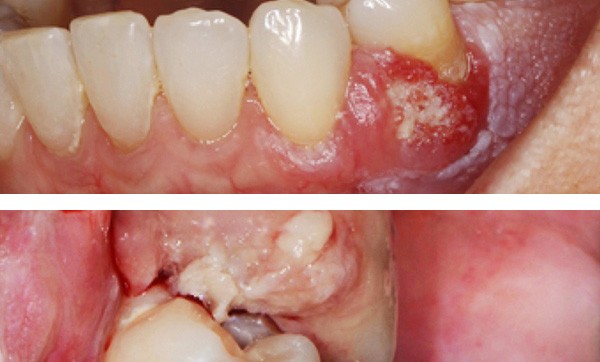

Examen clinique. On observait un remaniement de la fibromuqueuse gingivale vestibulaire et une tumeur gingivale vestibulaire intéressant principalement la papille interdentaire entre 33 et 34, avec une extension postérieure érythémateuse. Les limites de la lésion étaient assez nettes. Dans sa partie antérieure, il existait une zone papillomateuse blanchâtre où la pression faisait sourdre une substance blanchâtre, de consistance pâteuse. La gencive en dessous et en arrière de la lésion était recouverte par une kératose dont la surface avait un aspect framboisé.

L’examen histopathologique de la pièce d’exérèse a montré que la surface de la lésion était tantôt plane, tantôt papillaire, avec par endroits une épaisse couche de parakératose. L’épithélium comportait une alternance de zones atrophiques et de zones hyperplasiques. En profondeur, il existait un carcinome épidermoïde bien différencié dont certains lobules étaient centrés…